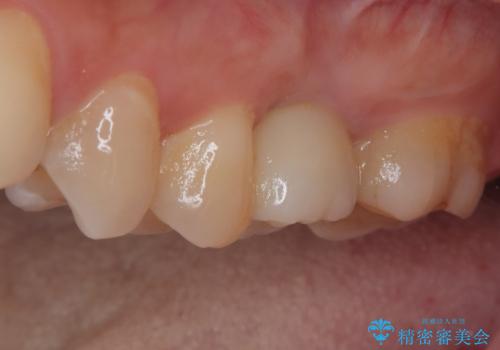

インプラント治療をきっかけに、銀歯を全てセラミックに替えていきました。

人の目を気にせずに、大きく口を開けて笑えるようになりました。